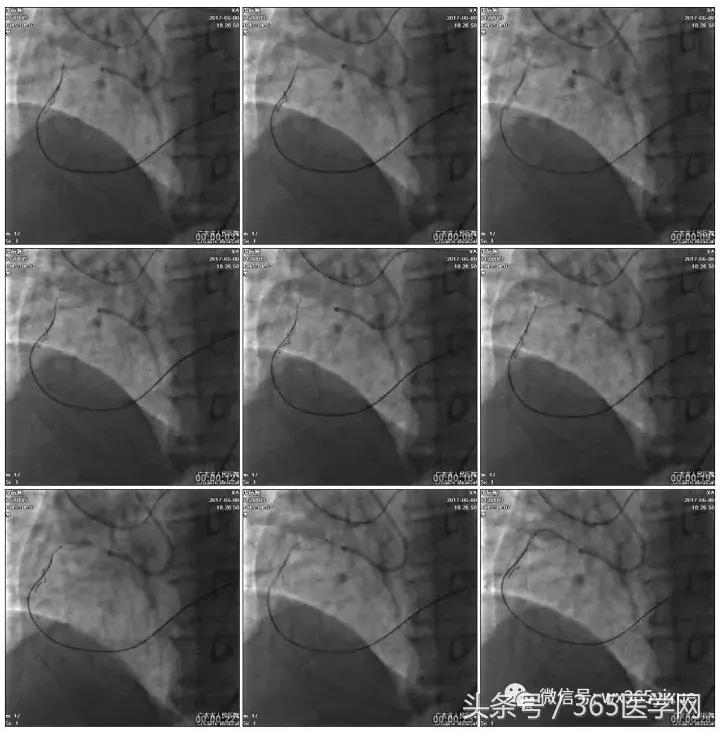

首先:IVUS指导下干预LAD

4.0mm*13mm药物支架

RCA闭塞段球囊扩张后IVUS